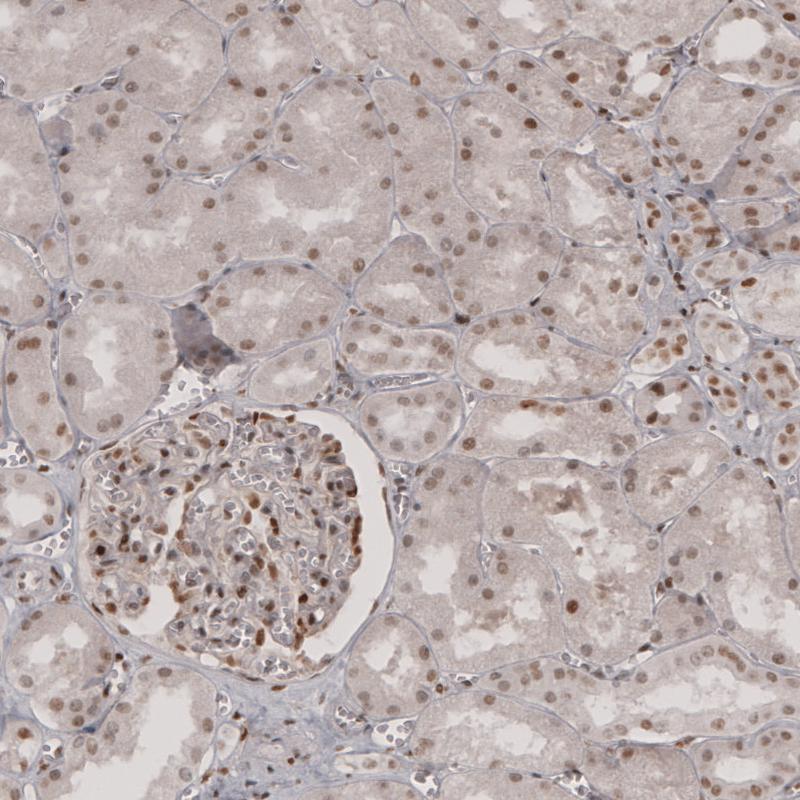

Immunohistochemical staining of human placenta shows moderate to strong nuclear positivity in trophoblastic cells.